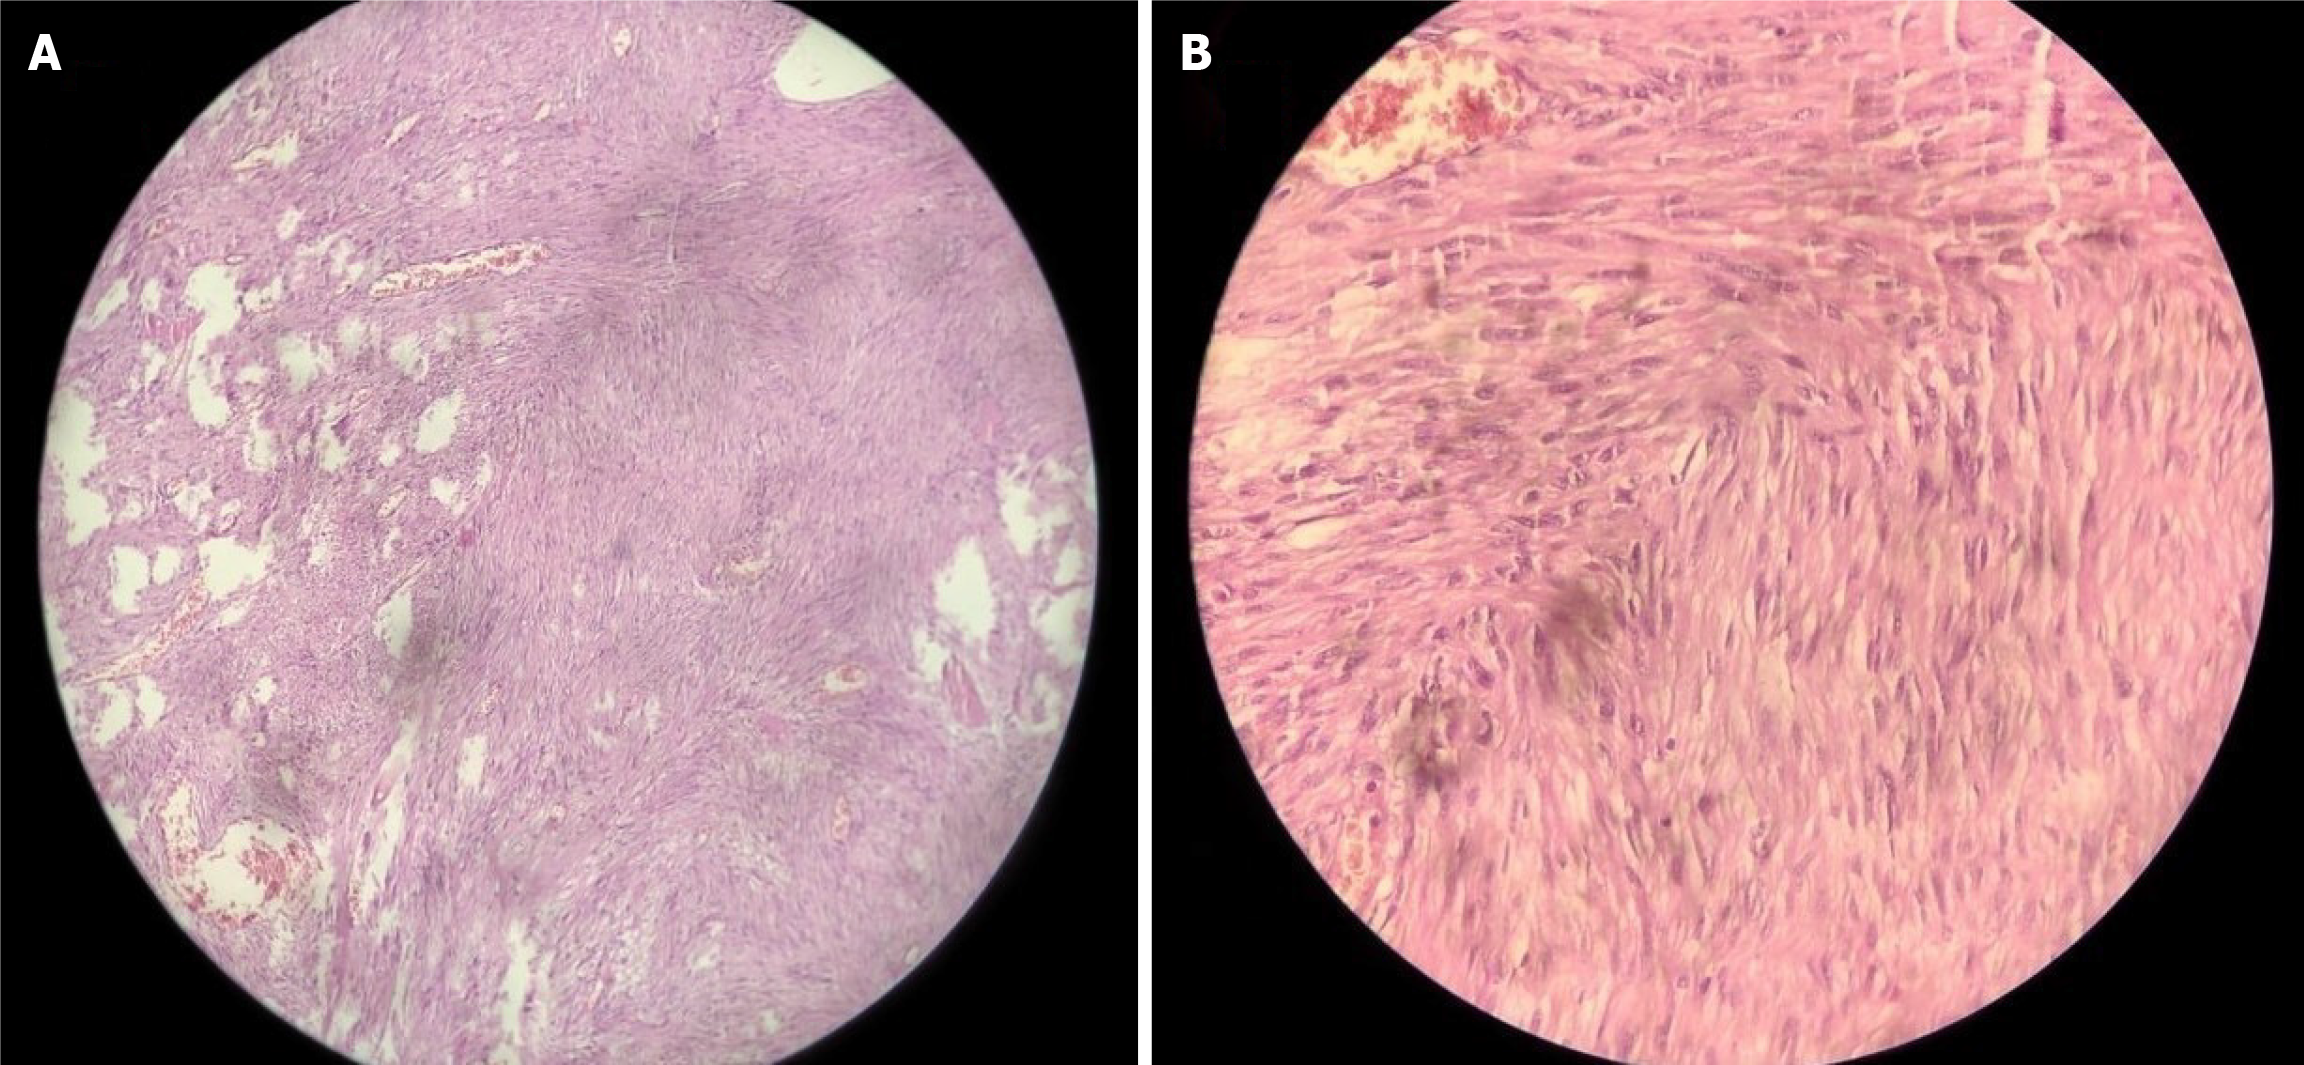

Figure 2 Histopathological image of postoperative jejunal specimen.

A: A 10× view of a submucosal tumor comprising spindle cells arranged in a long, fascicular pattern; B: A 40× view of spindle cells showing minimal pleomorphism mild hyperchromasia, low mitotic index, without any necrosis or epithelioid cells.